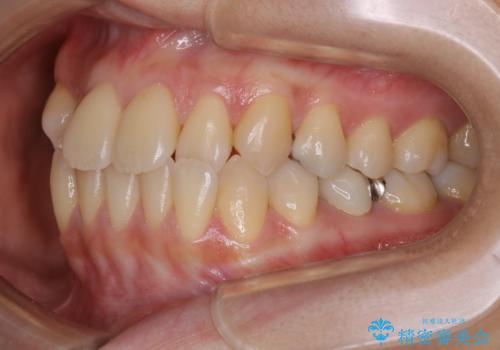

前歯が内側に入っている:インビザライン治療

- 上の前歯は内側に入っていることが気になりご相談にいらした方です。インビザラインにて治療を行いました。

1週間でのマウスピース交換を指示していましたが、20時間以上使えない時があると不安との事で、2週間ごとの交換にしていました(実際はほとんど20時間以上使用できていたようです)。治療終了まで時間はかかりましたが、最終的に綺麗に並べることができ、大変喜んでいただけました。